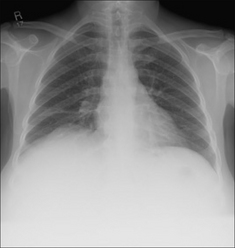

Figure 28.2 Acute dyspnoea. Lungs clear. Both domes of the diaphragm are high. Apply Golden Rule 1—clinical details are crucial. Abdomen is distended with a succussion splash when shaken. CXR conclusion—ascites displacing the diaphragm upwards.